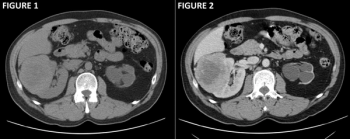

A 68-year-old woman is undergoing staging scans for gastric cancer. An image from her CT shows an abnormality. What is the diagnosis?